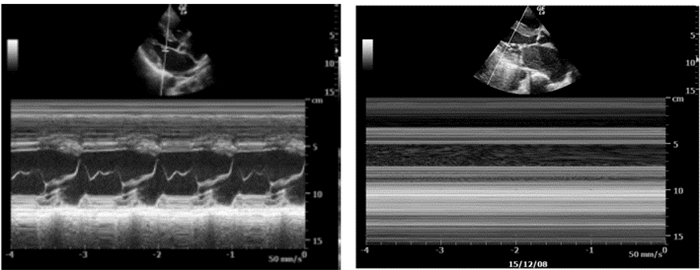

3.4.3 心肺复苏中超声诊断步骤及流程在心肺复苏中,为了避免超声检查对胸外按压的干扰,在心脏按压过程中实施心脏扫描,剑突下四腔心脏切面是最为理想的视窗。首先心脏超声可探及心脏运动(图 37),研究表明心脏骤停的患者被超声确认为心肌运动缺失的心搏停止时,其生存的希望极其渺茫。其次,超声检查还可以帮助寻找导致心脏骤停的可逆性病因。

| 图 37 M超判断心肌运动缺失情况(该图片由华中科技大学同济医学院附属协和医院重症医学科采集) |

具体超声诊断流程见图 38。